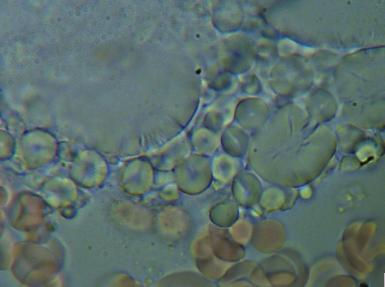

Komórki grzybów. W zależności od tego w jakim stopniu organizm zaatakowany jest przez grzyba widoczny jest obraz pojedynczych komórek lub całych kolonii i wtedy możemy mówić o bardzo niebezpiecznej dla organizmu grzybicy.